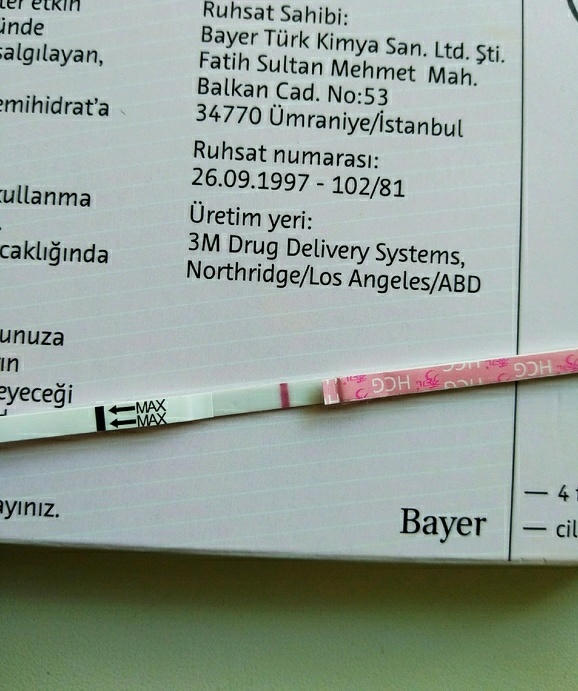

Наконец-то нашла время для того, чтобы поделиться с вами нашей радостью!🕊️ У нас получилось!🤗 И я просто не могу передать, как я счастлива!)) Ведь, казалось, совсем недавно я пришла на первый прием к Ре)) А теперь пишу этот пост) Правда из больницы🤒🤕 Дальше ооочень много букв и много фото (тесты, динамика, хгч, узи и т.д.) Кому интересно, прошу подкат ⬇️ Начну с того, что подсаживали нам 2х трехдневочек, и я даже не думала мочить тесты раньше 10 дпп, но на 3-4 дпп со мной творилось нечто ужасное (простите), мой кишечник разрывало, бурление в животе не оставляло меня в покое ни на минуту, и я заподозрила имплантацию) Где-то на сайте я встречала похожие истории про расстройство кишечника и положительный результат. С планирования прошлой беременности у меня завалялись китайские тесты с Джума, и они не давали мне покоя)) На 7 дпп в обед без особой надежды на вторую полоску (рано, ведь у нас 3х дневки) замочила китайский тест, и ..... не отводя от него глаз, я видела как, высыхая на тесте, появилась ОНА! // Бледная, но она есть!🤗